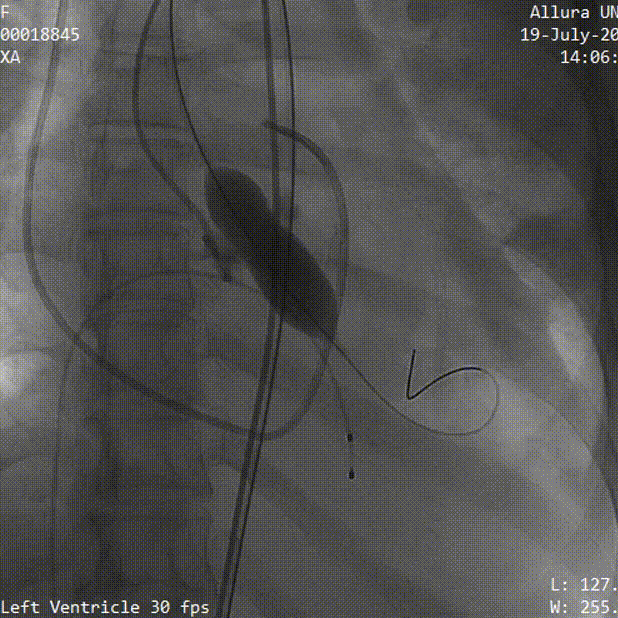

2.18mm球囊预扩,腰征明显,冠脉显影良好,无明显瓣周漏

18mm球囊预扩